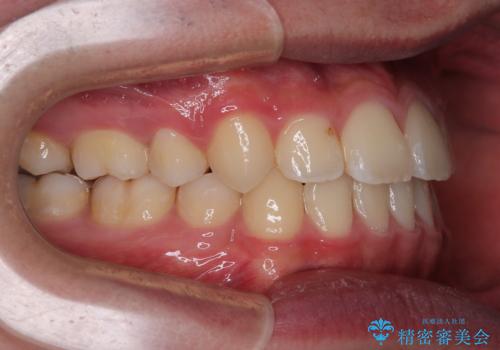

上顎骨に対して下顎骨がやや前方位に位置しているため、下顎前歯をあまり内側に移動させることができず、口元の突出感改善は期待以上にはならないと予測しておりましたが、満足いくの引っ込み具合となりました。